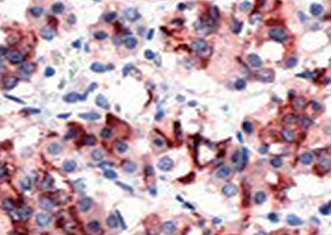

PRL 鼠抗人 PRL 抗体试剂(免疫组织化学)

| 预处理:高pH热修复 | 阳性部位:细胞浆 | 阳性对照:胎盘/垂体瘤 |

| 简介:PRL(Prolactin,催乳素)是由垂体前叶嗜酸性细胞分泌的一种激素,可促进乳腺发育和乳汁分泌。该抗体主要用于标记垂体催乳素细胞及其肿瘤,有助于垂体肿瘤功能性分类的研究。 | ||

| 垂体瘤石蜡切片,用 PRL(GT2161)染色,细胞浆阳性,DAB 显色。 | ||